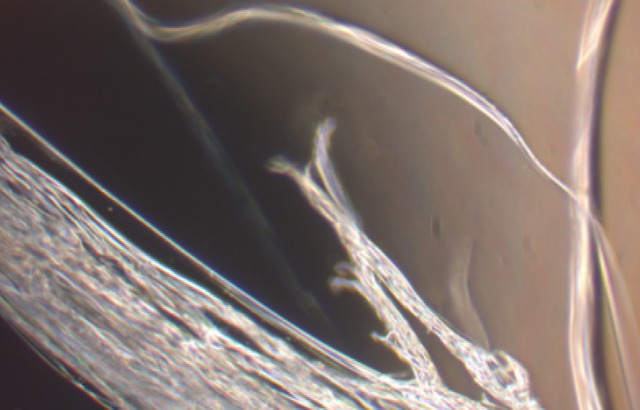

This confocal microscopy image shows cilia (in red) are the thin hair-like structures only a few 100th of a millimetre long. article News story: Manipulating the antennae on cells promises new treatments for osteoarthritis

Bioengineers from Queen Mary University of London (QMUL) have shown for the first time that lithium chloride, a common drug used to treat mental health disorders, could offer an effective treatment against osteoarthritis by disrupting the length of the cells’ antennae called primary cilia.